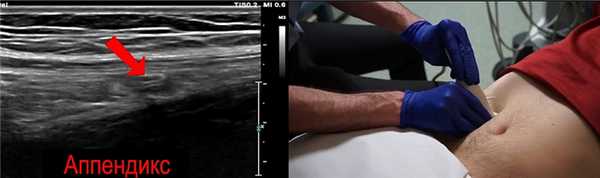

Мы нашили небольшую трубчатую структуру. Это и есть аппендикс

Полезный анатомический ориентир - поясничная мышца. Аппендикс часто можно увидеть над поясничной мышцей